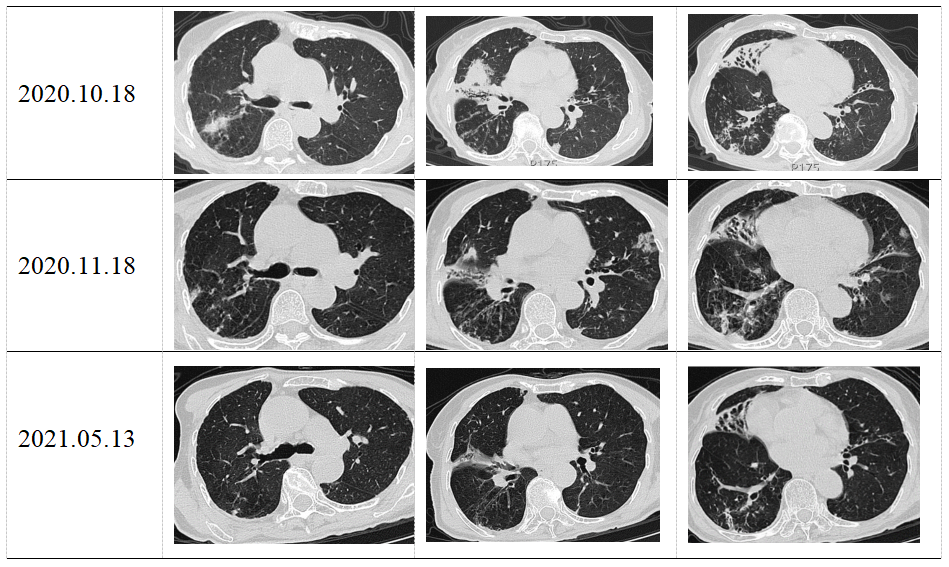

其它 肺奴卡菌病 写美篇奴卡菌肺炎的ct表现(进展期) 影像学缺乏特征

图片尺寸1280x812